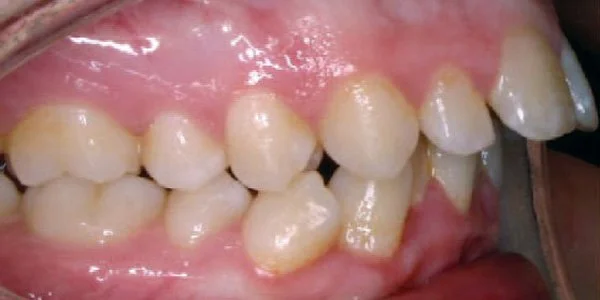

Anterior Crossbite

Top teeth are behind bottom teeth.